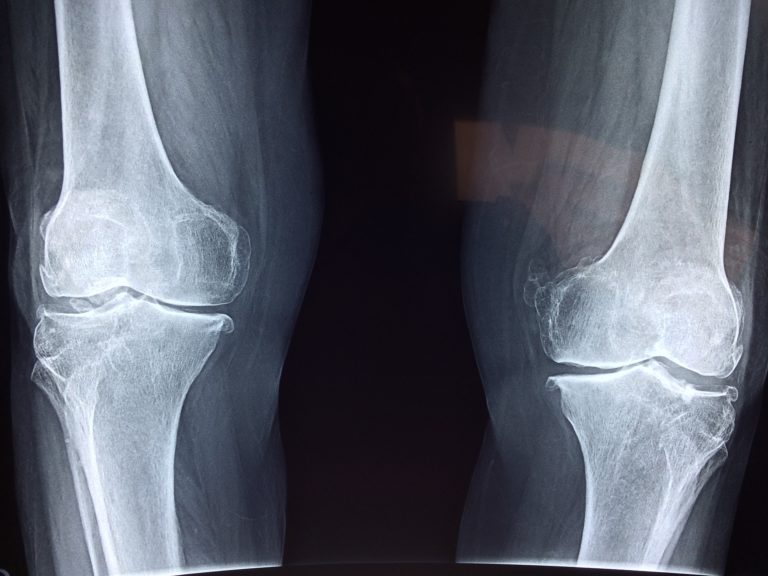

Jeśli doświadczasz opuchniętych kolan, zawsze zaleca się wizytę u lekarza. Jednak, mam sprawdzony domowy sposób na ból, obrzęk, a nawet wodę w kolanie. To bardzo skuteczny okład, który możesz przygotować w minutę.